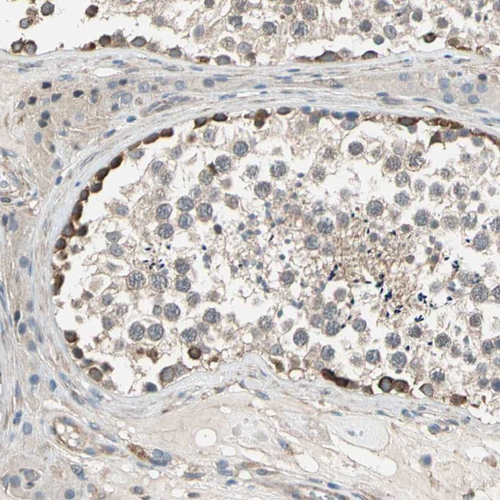

Immunohistochemical staining of human placenta shows weak to moderate cytoplasmic positivity in trophoblastic cells.